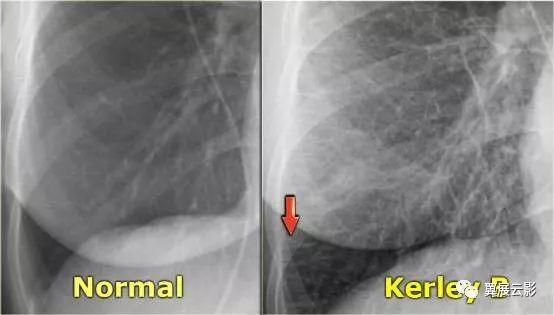

Kerley B线:是由于肺间质水肿引起小叶间隔增宽,在两肺下叶外侧可形成水平线状影,常位于肋膈角区,为长约1-3厘米、宽约1-2毫米的水平横线,一般垂直于侧肋胸膜(位于肋膈角上方与胸壁或膈肌垂直的条状影子),是肺小叶间隔内积液的表现。

CT的放大图像可见清楚的显示垂直于侧胸壁的小叶间隔増厚,即我们所说的Kerley B线。